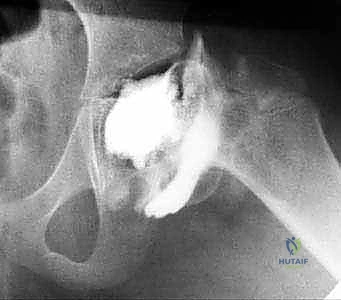

رأب نصف مفصل الورك لكسور عنق الفخذ: دليل شامل لاستعادة الحركة مع الأستاذ الدكتور محمد هطيف في صنعاء

تعرف على رأب نصف مفصل الورك لعلاج كسور عنق الفخذ. دليل شامل للتشخيص، العلاج، والتعافي تحت إشراف الأستاذ الدكتور محمد هطيف، أفضل جراح عظام ف…